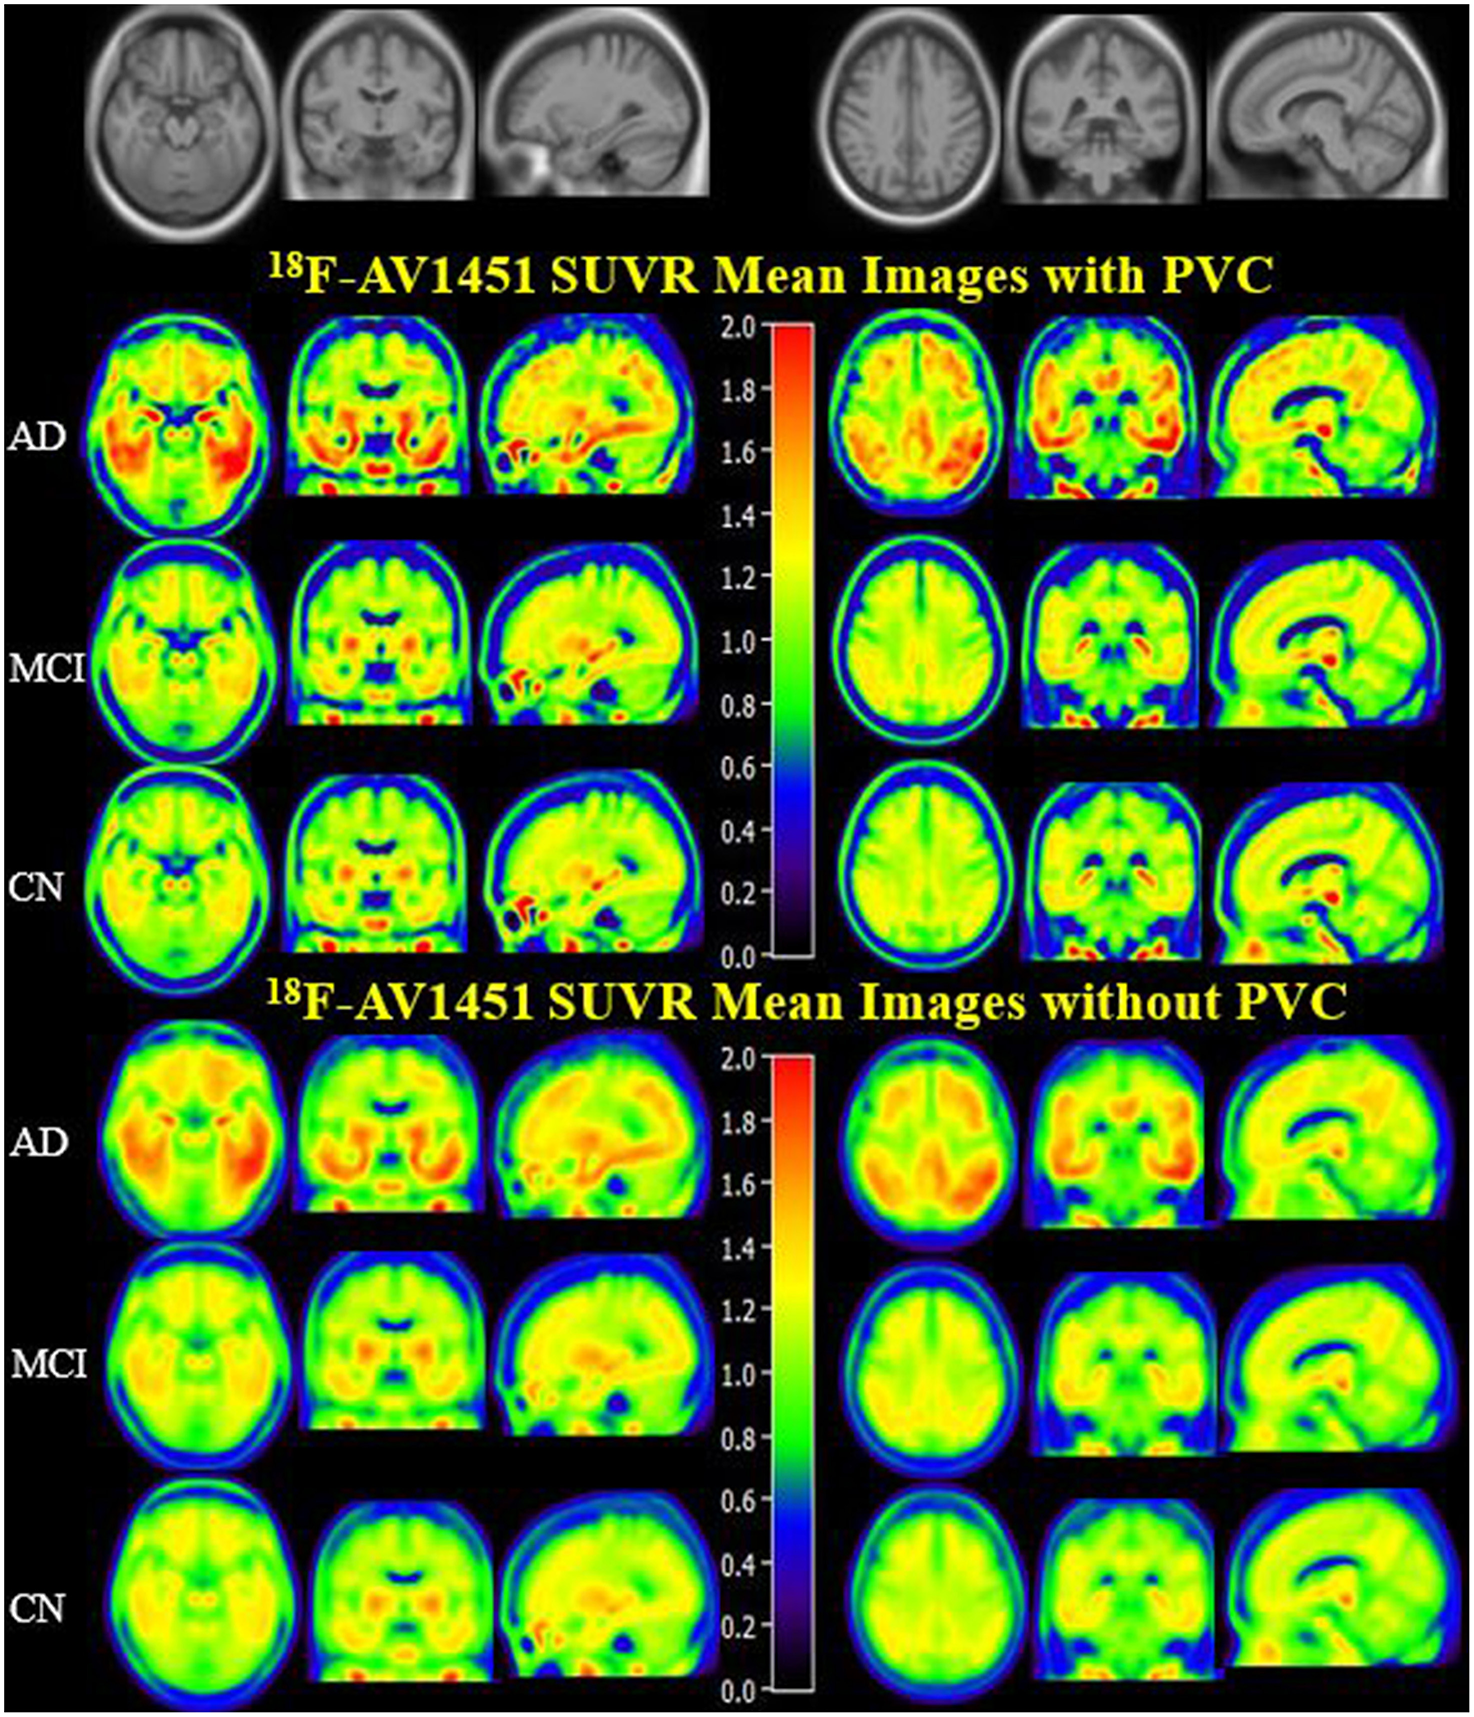

PVC for this study was used to decrease off-target binding in choroid plexus close to the hippocampus, basal ganglia, and brain atrophy. In order to create an anatomical visualization of the effects of PVC on spatial resolution and image contrast, we displayed mean 18F-AV1451 SUVR images of CN, MCI, and AD with and without PVC in Figure 1, which clearly showed an increased image spatial resolution and contrast after PVC in most cortical and subcortical ROIs. Brain 18F-AV1451 SUVR patterns were visually consistent with previous post-mortem and in vivo PET studies (1, 20, 21).

Figure 1

18F-AV1451 SUVR Mean Images with PVC and non-PVC. Mean images generated by computing the mean of images from AD, MCI, and CN participants separately. The upper images have been corrected with PVC, whereas the lower images without PVC.

It was reported that PVC has improved the tau PET quantification (23, 41). To deal with off-target binding and brain atrophy on PET quantification, we performed the PVC routinely in this study. In CN group, 85% ROIs were statistically different with or without PVC. However, the percentage fell to 73 and 35% in MCI and AD group, respectively. PVC showed better adjustment of SUVRs, especially in CN group. As visualized directly in 18F-AV1451 SUVR mean image, PVC improved the spatial resolution and image contrast. The amygdala SUVR with or without PCR in AD brain was 1.66 and 1.99, which almost increased by 20% after PVC. In comparison of SUVRs of posterior precuneus region between MCI and AD group, the statistical status was evenly changed.